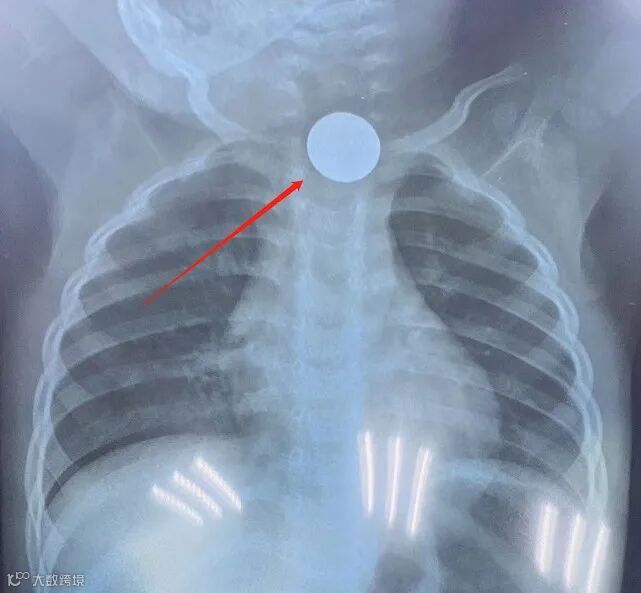

近日,一名一岁半男童在家自己误吞了一枚1角钱硬币,两天内家长都没有发现,因男童出现吞咽困难,进食呕吐,遂送来市人民医院急诊科就诊,拍胸片时才发现硬币卡在男童食道里。

这个卡在孩子食道2天的硬币被医生妙手一分钟取出,家长当时几乎惊呆了,“家长的表情是千恩万谢的,因为孩子不需要住院全麻手术,时间短费用低。”,肖静说。

肖静介绍,一般情况下,食道异物取出Foley法只适用于卡在食道里的类似硬币、戒指等圆形物体,在门诊处理便可,不用收入院,也不用全麻在手术室里手术。在临床上,市人民医院耳鼻咽喉科医生运用了很多次这个方法取出食道异物。